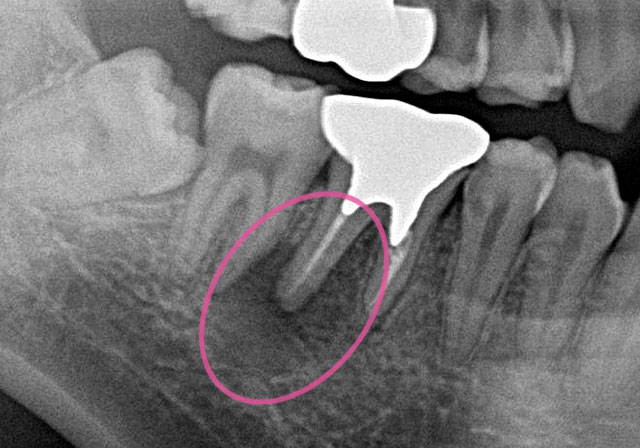

長年放置され悪化した親知らずの抜歯日航ビル歯科室親知らず抜歯なら川崎駅徒歩1分の歯医者。

長年放置され悪化した親知らずの抜歯日航ビル歯科室親知らず抜歯なら川崎駅徒歩1分の歯医者。